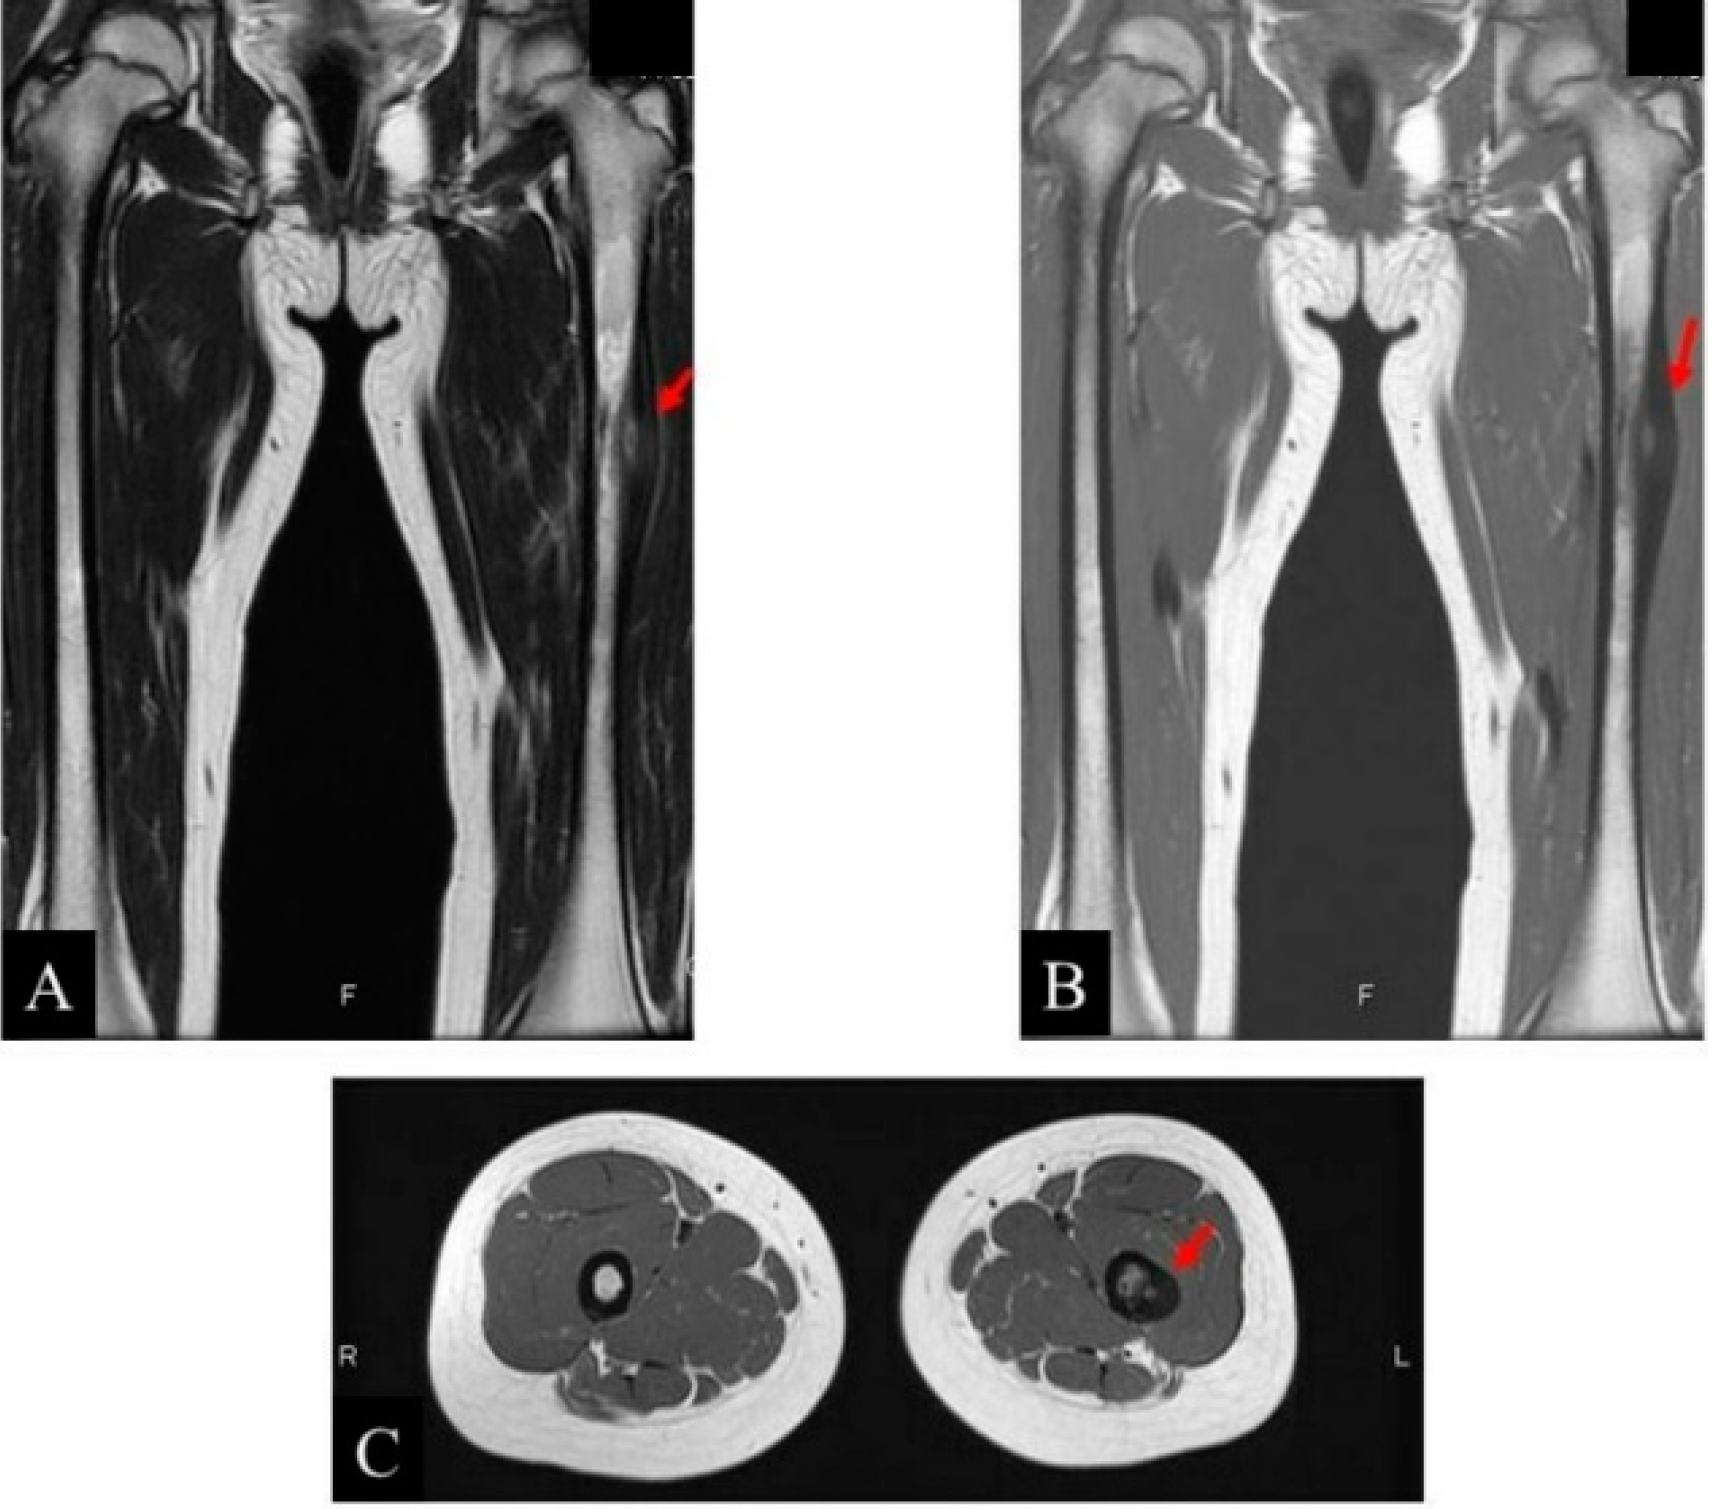

2. Case Presentation

- Clinical and radiological evaluation of the osteoid osteoma.